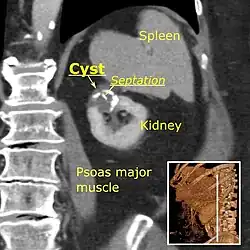

Category IIF

A Bosniak category IIF cyst. This one is 3 cm wide, with calcifications within its wall, seen as very radiodense (white in this presentation) areas in its margins. There is also a septation which is calcified. Yet, the cyst does not show enhancement (uptake of contrast).

This category includes renal cysts with multiple thin septa, a septum thicker than hairline, slightly thick wall, or with calcification, which may be thick. It also includes intrarenal cysts larger than 3 centimetres (1.2 inches) if:

• there is no contrast enhancement (otherwise category III).[8]

• there is high attenuation or there is a maximum 25% of their walls visible outside the kidney (otherwise category II).[4]

Category IIF cysts have a 5–10% risk of being kidney cancer, and therefore follow-up is recommended. However, there is no consensus recommendation on the appropriate interval of follow up.[8]